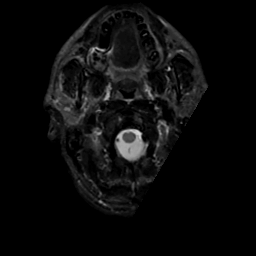

MR Study #15, June 9, 1991 -- Slice #1